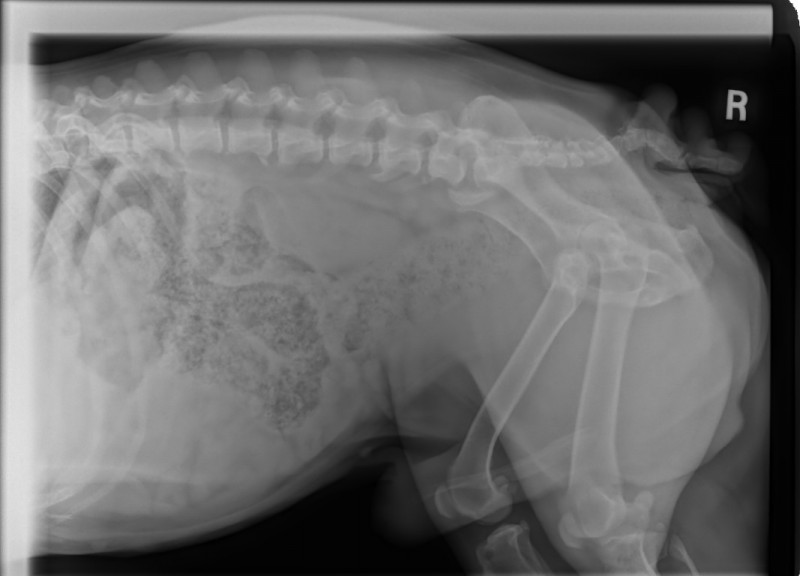

I took a look over his eyes and, they look fine. I looked at his chin and feet and, yes, they are definitely not great. I also looked at the one fold his temp foster wanted me to check and, it is slightly infected.

I told his temp foster mom that, my plan was to take him back for about 10 days, heal him up and, then bring him back. Should he react again, then we know for sure that the carpet, perhaps even laundry detergent, fabric softener, and, I did not even ask if they use anything like Febreeze, could well be the problem. We will know for sure then, that we do not want to see him in an approved adoptive home that has any carpets and, would have to be careful about other products used around him.

Even per his Vet at KAH, that he is on Baytril and, that he is battling these infections, is a bit concerning.